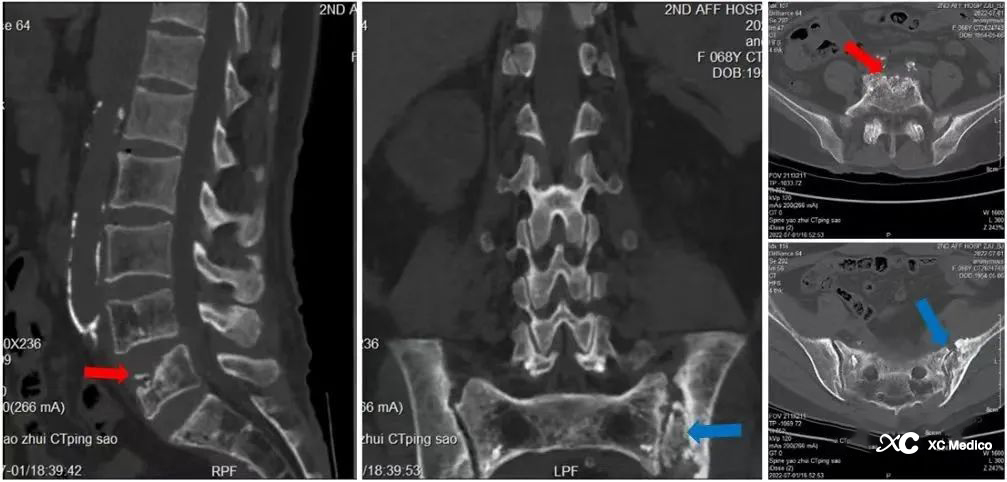

Примечание: обширный остеопороз поясничного и крестцового таза. Разрушение антеросочериорного края поясничных 5 позвонков со склеротической гиперплазией края (показанная красной стрелкой). Прилегающая гиперплазия рубцов. Разрушение левого сакровистой суставы с разрушением боковой суставной поверхности подвздошного подвздошного ткани, множественными внутренними мертвыми костями и локализованной гиперплазией тканей, похожей на рубцов (показано синими стрелками).